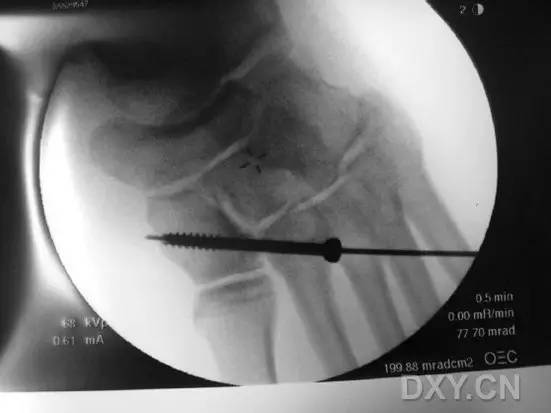

完成术区暴露和维持复位后,在 X 线透视下,自足底方向经第 2 跖骨基底背外侧向内侧楔骨置入导针,采用空心钻经导针钻孔,然后将一枚 4.0 - 5.0 mm 直径适当长度的半螺纹空心螺钉经导针置入(图 4)。

图 4. 术中 X 线透视下,经第 2 跖骨基底背外侧向内侧楔骨置入 Lisfranc 螺钉